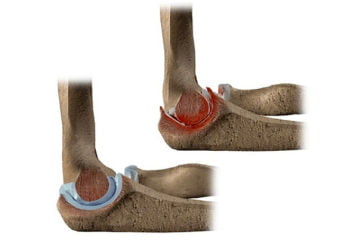

Остеоартроз локтевого сустава: симптомы, лечение и профилактика

Остеоартроз локтевого сустава 1-2-3 степени. Лечение на разных стадиях. Медикаменты и хирургия. Советы специалистов для профилактики.